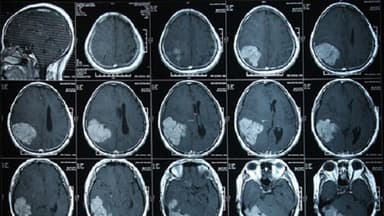

Chụp CT sọ não là phương pháp chẩn đoán cận lâm sàng thường được các bác sĩ chỉ định để kiểm tra các bất thường tại vùng đầu. Thông qua các kết quả bác sĩ có thể xác định được nguyên nhân của bệnh và có phương hướng điều trị phù hợp.

Chụp CT sọ não hay còn có tên gọi khác là chụp cắt lớp vi tính sọ não. Đây là chỉ định cận lâm sàng giúp bác sĩ có thể kiểm tra các triệu chứng chấn thương vùng đầu hoặc không do chấn thương như hôn mê không rõ nguyên nhân, liệt, đau đầu, chóng mặt…

Chụp CT sọ não sử dụng tia X để quét tia từ gốc mũi tới đỉnh đầu người bệnh để lấy hình ảnh chi tiết nhất trong sọ não. Đầu đèn phát tia của máy chụp CT sọ não nghiêng về nhiều hướng khác nhau để ghi hình và cho nhiều hình ảnh từ các góc độ khác nhau.

Ngoài ra, bác sĩ cũng có thể chỉ định cho người chụp CT sọ não tiêm thuốc tương phản đường tĩnh mạch đối với một số trường hợp cần thiết. Thuốc tương phản có tác dụng làm tăng tương phản vùng bất thường, giúp kiểm tra sự lưu thông mạch máu, nhận diện khối u, viêm, áp-xe…